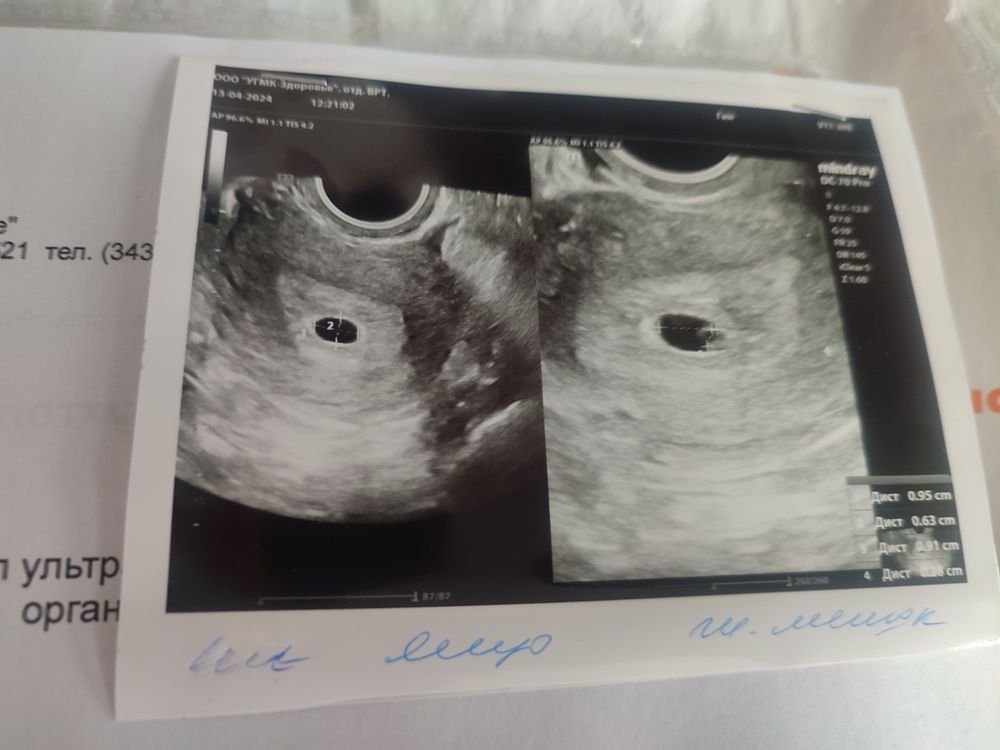

Елена , у меня сейчас только 5 неделя и 3 день )) но на УЗИ сходила все хорошо, но сердечко пока что не слышно )

На УЗИ. Отслойка, выкидыш, сосуды лопнули, полип, эрозия могут быть. Лучше перебдеть.